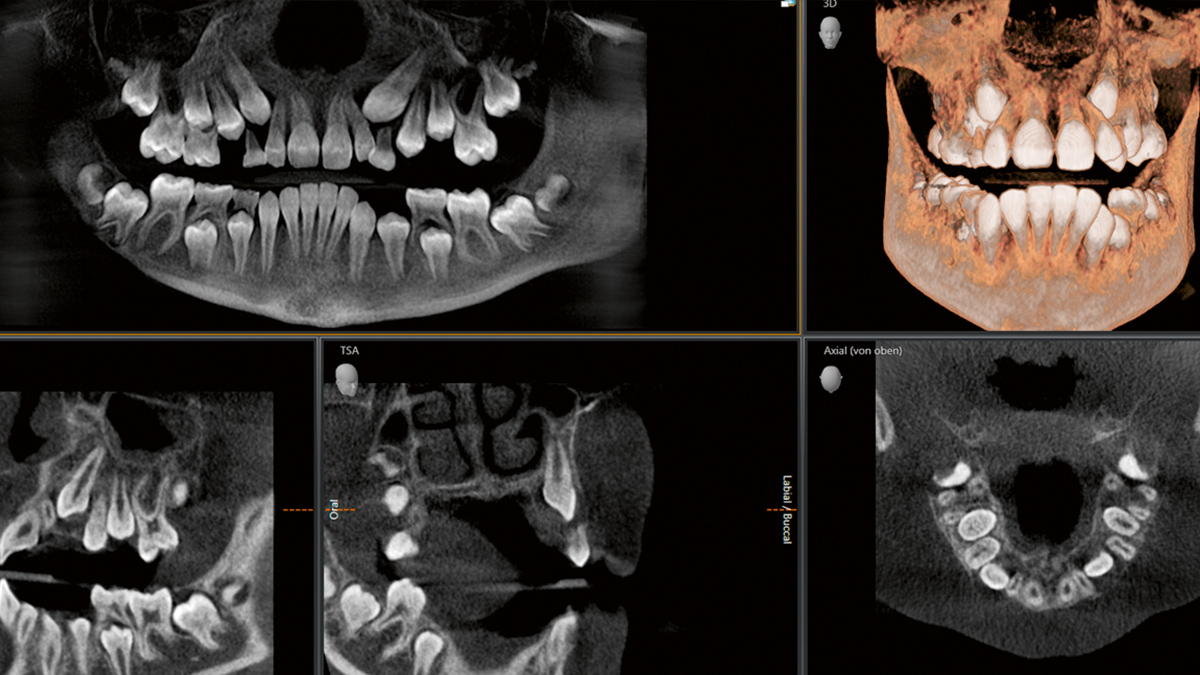

3D-Darstellung der Zahnstellung und Kieferstruktur

Mehrdimensionale Röntgendiagnostik des Gebisses

Digitales Röntgen bietet außerdem weitere Vorteile: Durch die digitale Verarbeitung der Signale sind höhere Auflösungen und auch Aufnahmen im Mikrometer-Bereich möglich, zum Beispiel im Zahnwurzelkanal. Zudem können wir damit auch Farb- und sogar 3D-Aufnahmen von Kiefer und Zähnen anfertigen. Diese räumlichen Aufnahmen bringen auch kleinste Details ans Tageslicht und ermöglichen uns somit eine deutlich präzisere Diagnostik.